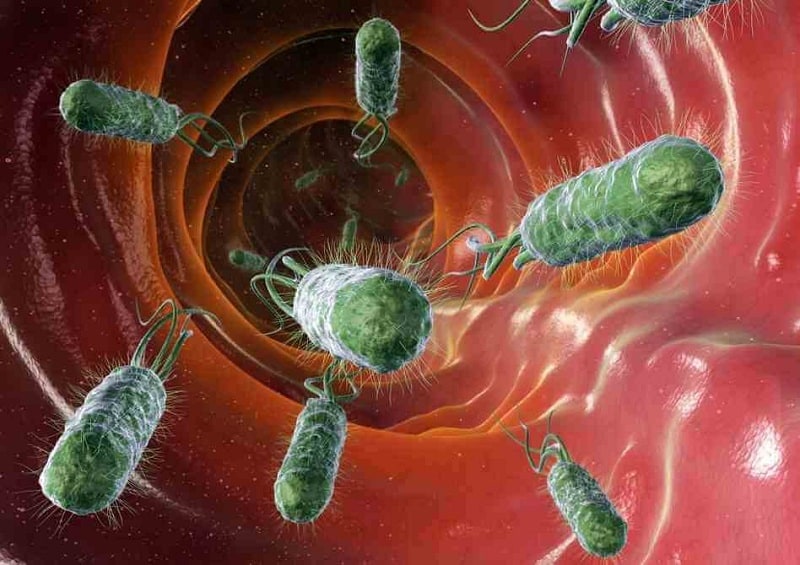

E.coli intestine infection

E.coli intestine infection